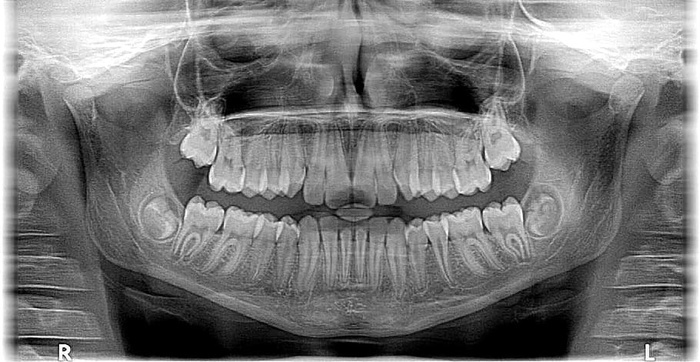

全景牙科x光,人类头骨和牙齿

x射线照片人类头骨x射线x射线照片伦琴牙齿